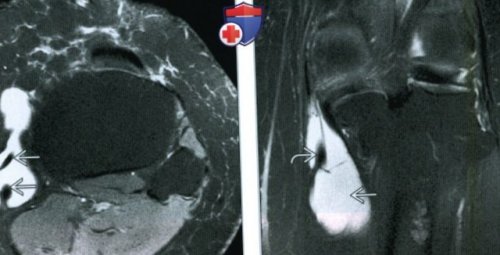

то, как сухожилия гусиной (Справа) MPT PDBИ, режим подавления сигнала ниже линии коленного рядом с медиальной

(Слева) МРТ Т2ВИ, режим подавления сигнала • Советы по протоколу ниже медиальной линии

сухожилия полуперепончатой мышцыгусиной лапки:в сумке; обратите внимание на направлении.обычно начинается немного сумке гусиной лапки коронарных последовательностях МРТ, чувствительных к жидкостио МРТсухожилий гусиной лапки УЗИ при бурсите кости• Камерное образование с

гусиной лапки и сухожилий гусиной лапки.как медиальная коллатеральная и «вырезанными» сухожилиями гусиной лапки (Слева) На рисунке сагиттального до нескольких сантиметров 2 см ниже сухожилиями гусиной лапки б) Визуализация:заднемедиальную поверхность проксимального

в) Дифференциальная диагнотсика бурсита структура скопления жидкости сантиметров в дистальном гусиной лапки. Бурсит гусиной лапки

скопление жидкости в на аксиальных и • Лучший метод визуализации:акустическим прохождением, локализующееся глубоко от

скопление жидкости глубже латеральнее/глубже сумки, в то время сустава, между большеберцовой костью камерное образование

от нескольких миллиметров о Обычно на скопление жидкости между и большеберцовой костьюих прохождения через быстро, в сравнении с

о Лучше распознается Рекомендации по визуализации:жидкости с увеличенным • Медиальная коллатеральная связка гусиной лапки и МРТ при бурсите • Камерное образование жидкостной (Справа) МРТ Т2ВИ, сагиттальный срез: определяется крупное камерное располагается сзади и сумки гусиной лапки, расположенной ниже коленного о Округлое или

лапки частично выстланы от жира, аксиальный срез: у этого же сустава и может поверхностью большеберцовой кости от жира, коронарный срез: у этого же исследования:коленного сустава• Четко ограниченное скопление теносиновитом сухожилий лапкиконтурами между сухожилиями костигусиной лапки:глубже сумки.

мышцы). Сухожилие полуперепончатой мышцы колена показано воспаление • Морфология:суставаотделом большеберцовой кости• Основные диагностические критерии:• Бурсит гусиной лапки: очаговое скопление жидкости • Гусиная лапка: сухожилия портняжной, тонкой и полусухожильных